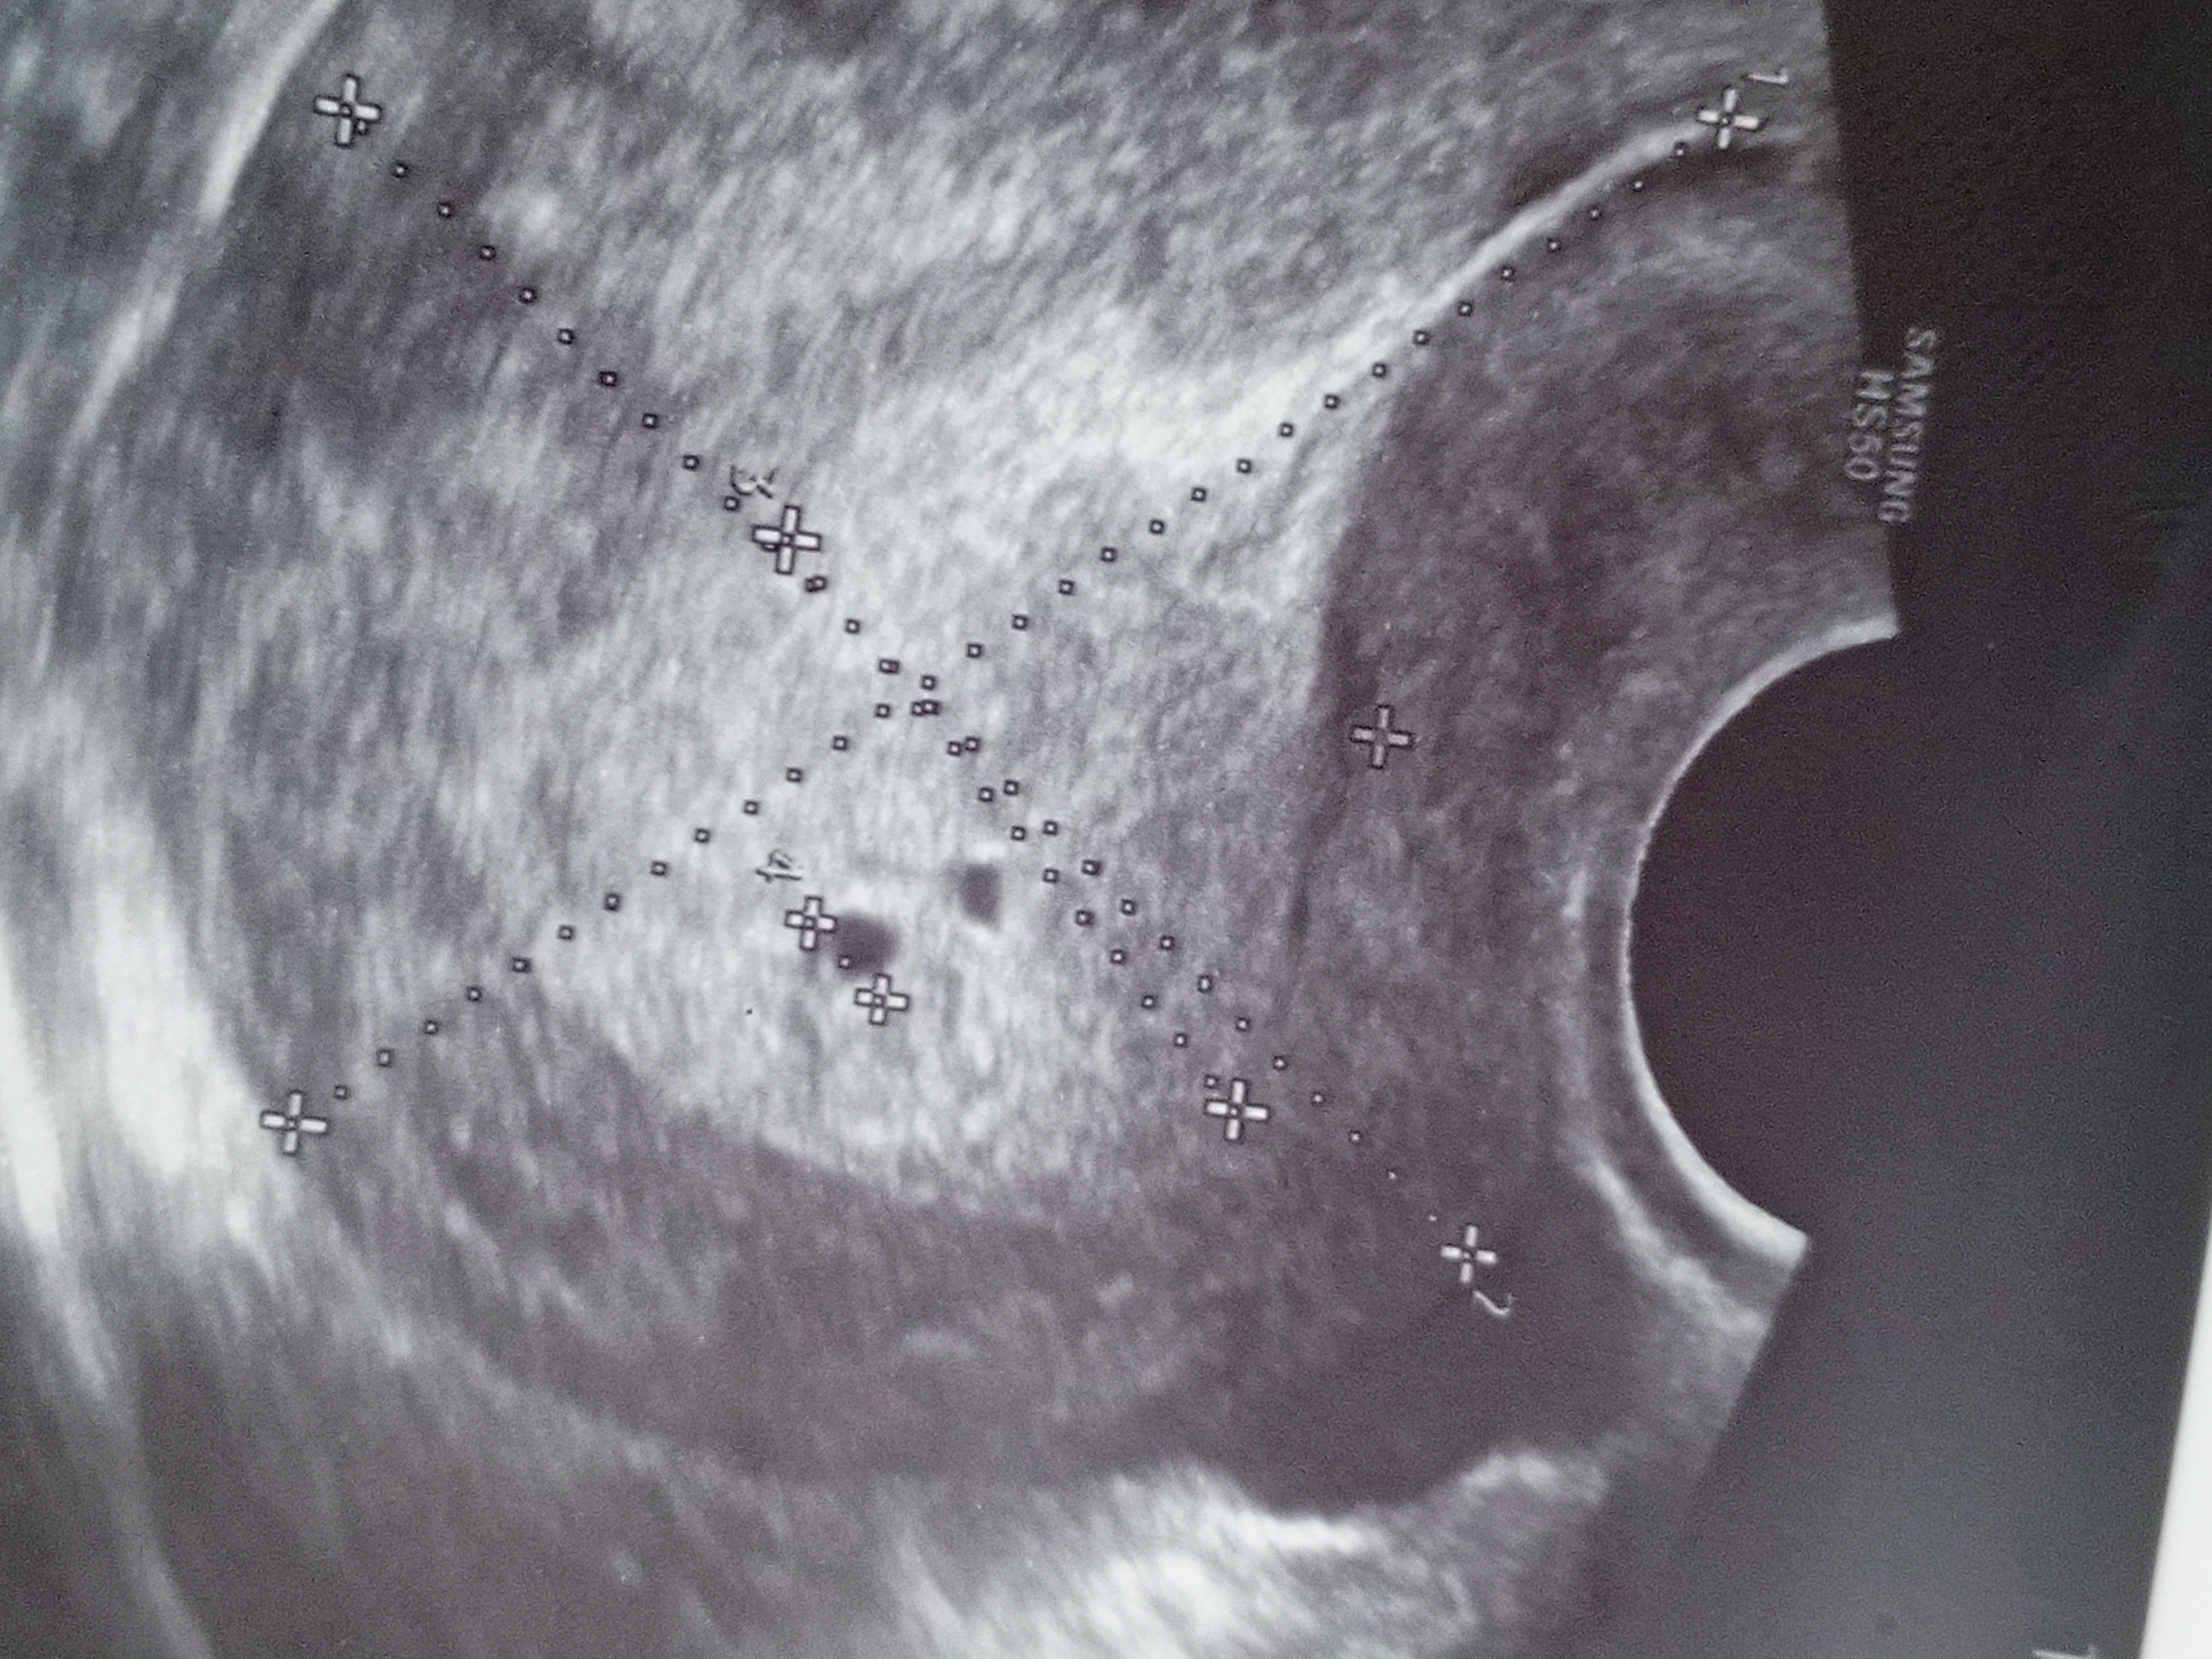

20 дпо это срок 2,6 от зачатия, соответственно 4,6 акушерских УЗИ соответстветствует сроку